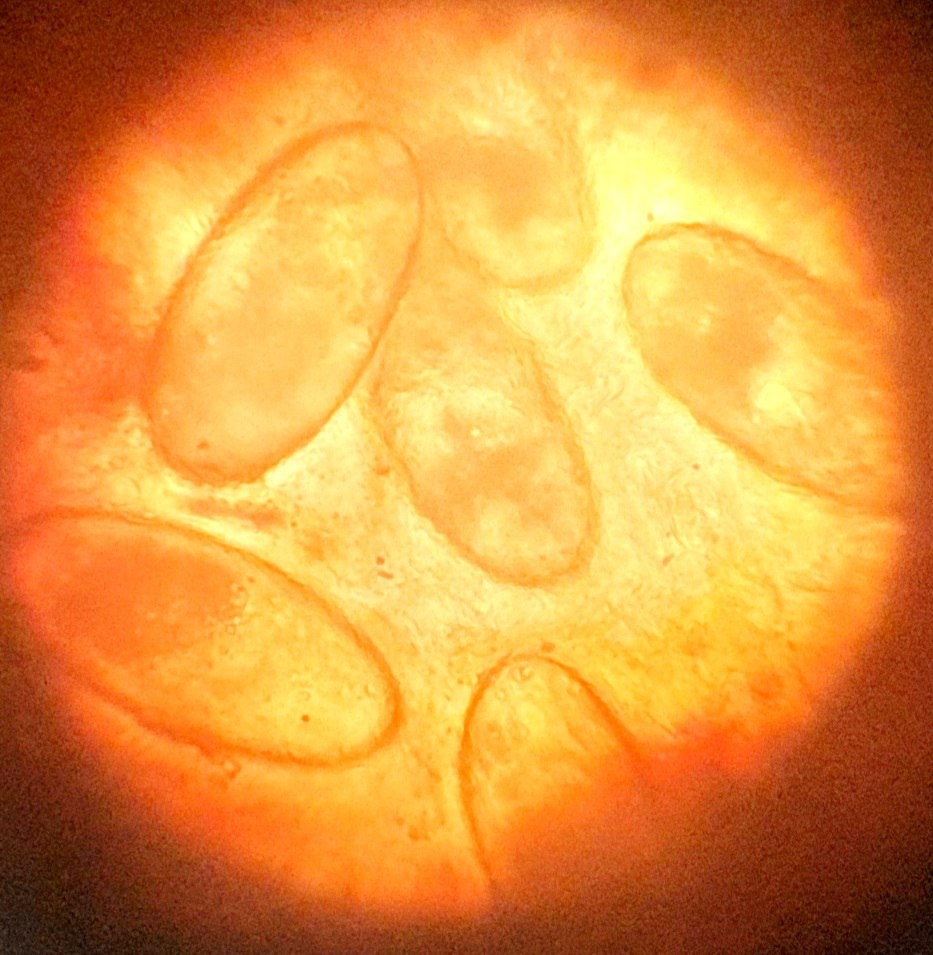

Пришла зима! Работаем с ушными клещами - отодектоз у кошки

Пришла зима! Работаем с ушными клещами - отодектоз у кошки. Препаратов для борьбы с данной патологией множество. Выбираем самые щадящие. Прогноз благоприятный. И самое главное, православных - с продолжающимся Рождественским постом! Потрудимся!